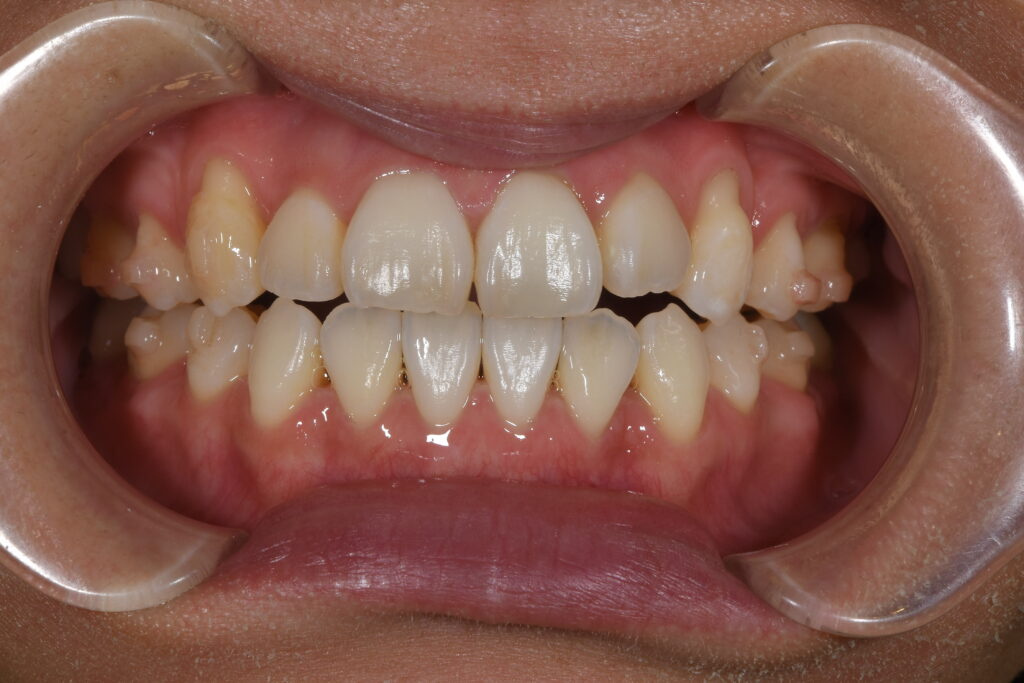

矯正開始1年の状態です。

【治療開始1年】

開口・抜歯矯正と治療難易度は高いですが、患者様がしっかりとマウスピースを装着して頂けているのもあり、1年でここまでの状態に改善しております(^^♪(もちろん、この状態から最終の状態へもうしばらく治療は必要です!)

矯正治療において、どうしてもスペースがなければ抜歯が必要になるケースもありますが、インビザライン矯正(マウスピース矯正)でここまでかみ合わせもしっかり改善することが可能になります。